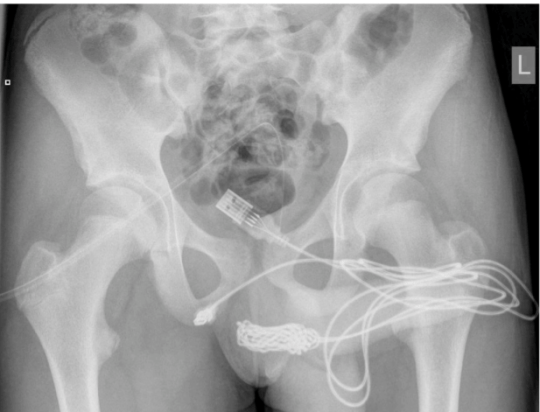

Chłopiec nie chciał się przyznać lekarzom, że za pomocą kabla USB, próbował zmierzyć długość penisa. Zrobił to dopiero, gdy jego matka wyszła z gabinetu. Medycy bezskutecznie próbowali wyjąć kabel. Po wykonaniu prześwietlenia okazało się, że jest to poważny przypadek.

Lekarze wykonali prześwietlenie

Lekarze wykonali prześwietlenie © Facebook

Przewód utknął w cewce moczowej nastolatka

Przewód utknął w cewce moczowej nastolatka © Facebook